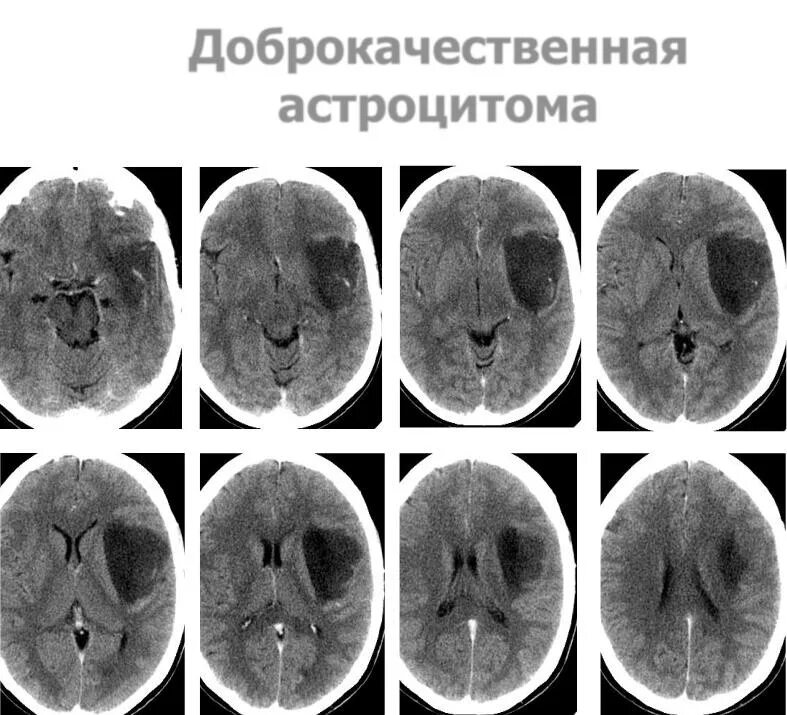

Астроцитома головного мозга прогноз после операции